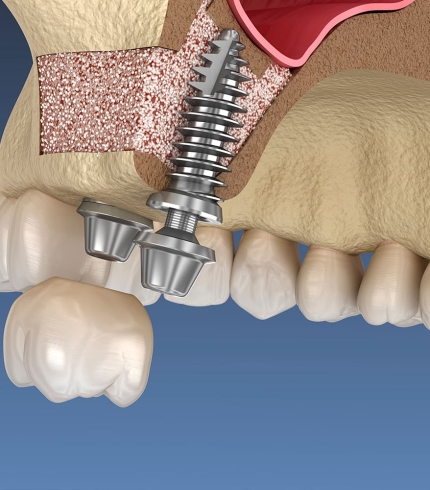

Çene Kisti Operasyonları yapılırken kist uygulanabiliyorsa tek parça halinde alınmaya çalışılır. Büyük ölçekli kistler önce küçültülür daha sonra cerrahi işlemle alınır. Çene kistleri çene kemiğinde ya da diş köklerinde bulanabilir. Eğer kist diş köklerindeyse operasyon sırasında kist ile ilgili diş ağızda bırakıldıysa dişe kanal tedavisi uygulanır ya da operasyon sırasında diş çekildiyse daha sonra ilgili dişe implant tedavisi uygulanır. Operasyon sonrasında bu süreç hem cerrah hem de hasta tarafından dikkat edilmesi bir dönemdir.